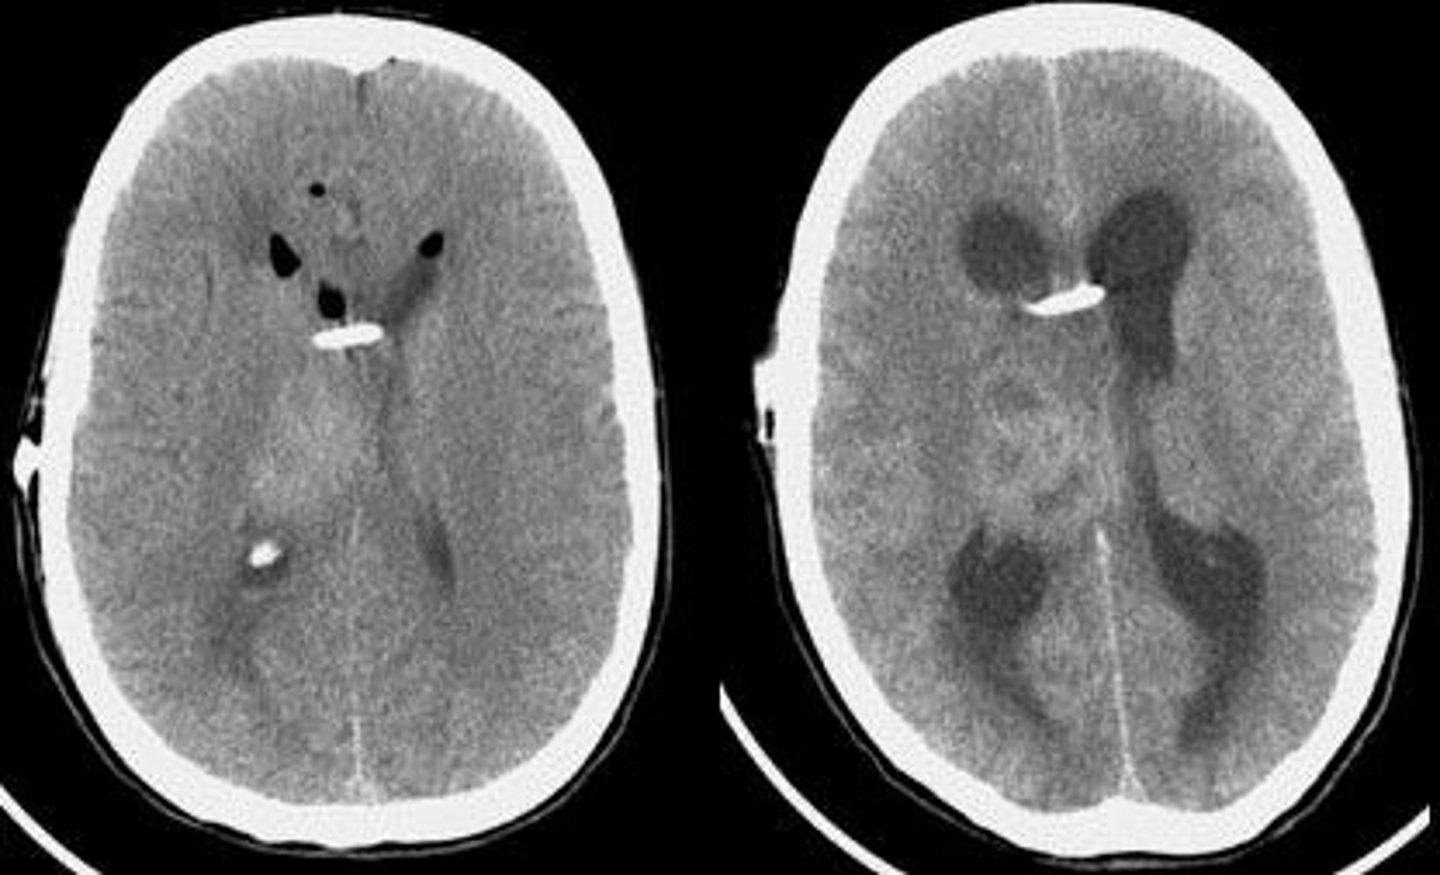

Meningitis

inflammation of the meninges of the brain and spinal cord

Bacterial Meningitis

Consists of gram positive and gram negative bacteria

Gram - Bacterial Meningitis

Consists if cocci and bacilli as well.